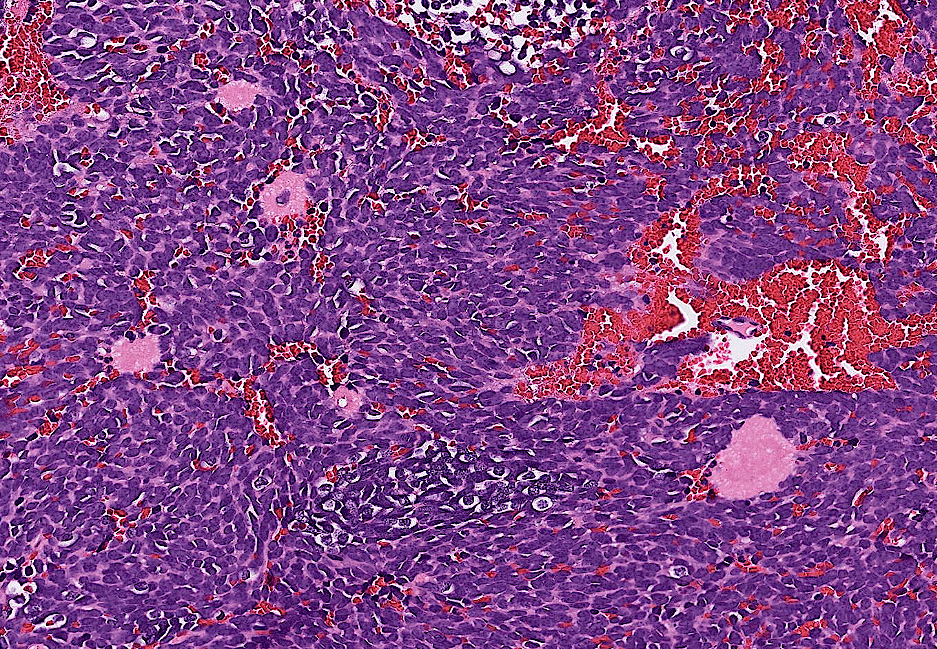

endometrial cancer